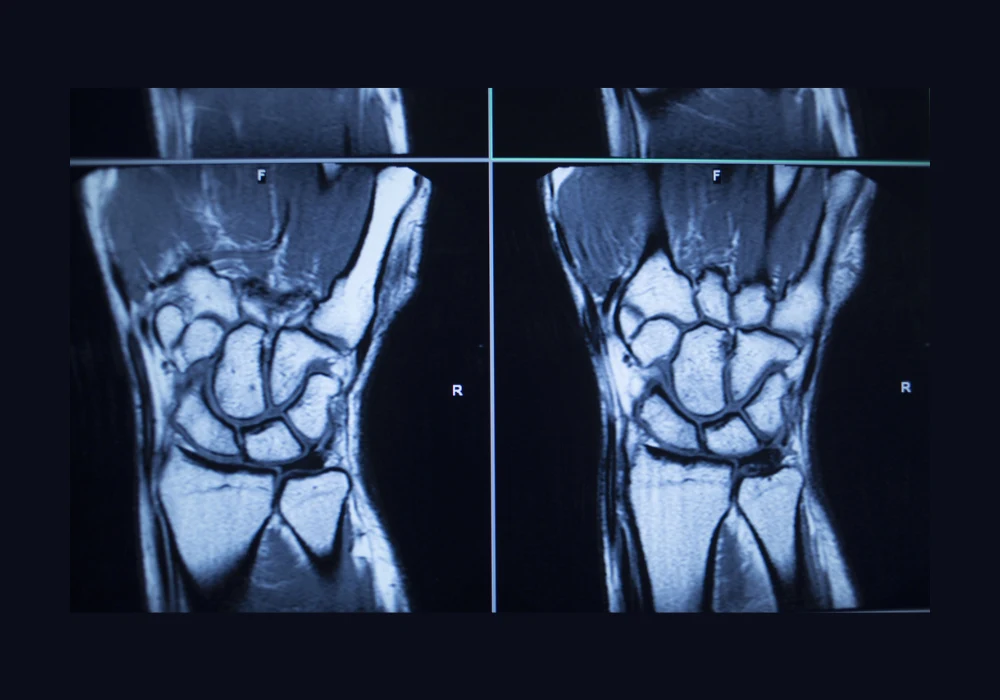

Magnetic resonance imaging (MRI) is an established diagnostic tool for musculoskeletal conditions of the upper limb, particularly the hand and wrist. Its high diagnostic accuracy makes it indispensable in clinical care, yet its use can also reveal findings unrelated to the reason for referral. These incidental abnormalities, ranging from benign variations to serious pathology, present challenges for both patients and healthcare systems. They may lead to additional tests, follow-up appointments or treatment, with implications for costs, clinical resources and patient anxiety. Data from a large tertiary centre in the United Kingdom provides detailed insight into how often such findings occur in hand and wrist MRI, their nature and the circumstances under which they are most likely to be identified.

Over a 14-year period, 2138 hand and wrist MRI scans were analysed after exclusions for incomplete or inappropriate cases. Of these, 490 scans, representing 22.9%, revealed at least one incidental finding. Incidentalomas, defined as incidental findings requiring further investigation or treatment, were identified in 67 scans, accounting for 3.1% of the total. This means that approximately one in four scans contained an unexpected anomaly, and around one in 30 required clinical follow-up.

Incidentalomas were most commonly located in bone, followed by the joints. Smaller numbers were found in muscle, mixed tissues, nerves and vessels. While many were benign, three cases were malignant, five were benign neoplasms, and the majority were clinically innocent anomalies such as ganglion cysts or anatomical variations. Almost all patients with an incidentaloma required clinical surveillance, and 19% underwent additional procedures. These included repeat MRI, ultrasound, CT scans and blood tests. The data demonstrates that incidental findings can significantly influence patient management, even when not directly linked to the original indication for imaging.